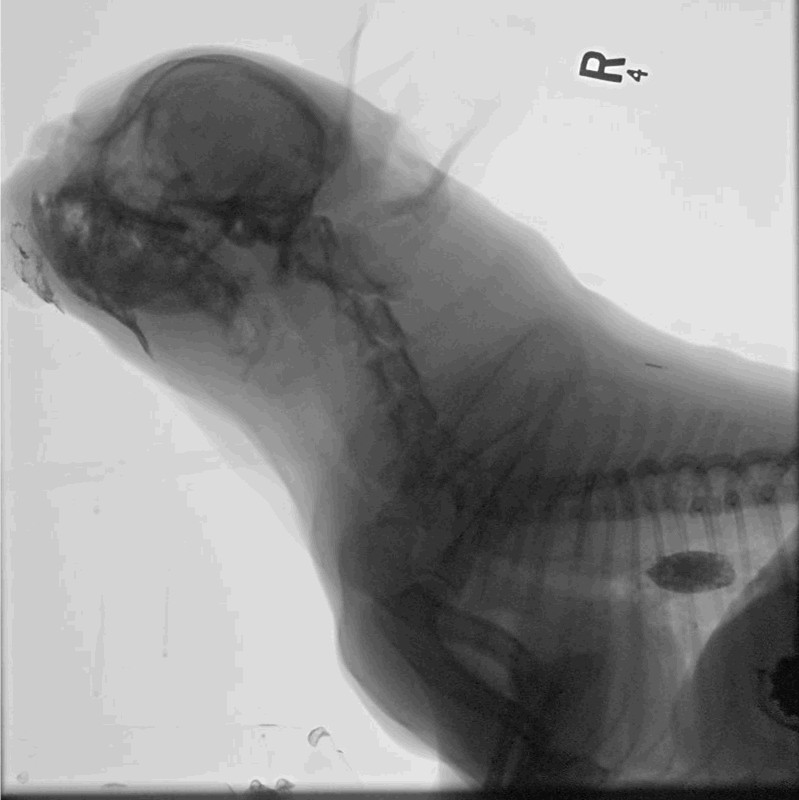

Fluoroscopy provides real-time dynamic imaging (continuous X-ray movie) of internal structures to aid with the diagnosis of conditions that may not be apparent on static radiographs. This allows for the evaluation of an in-action motion or motility of various structures to aid in the diagnosis of various dynamic diseases.

Dynamic tracheal collapse (video fluoroscopic dynamic airway exam)